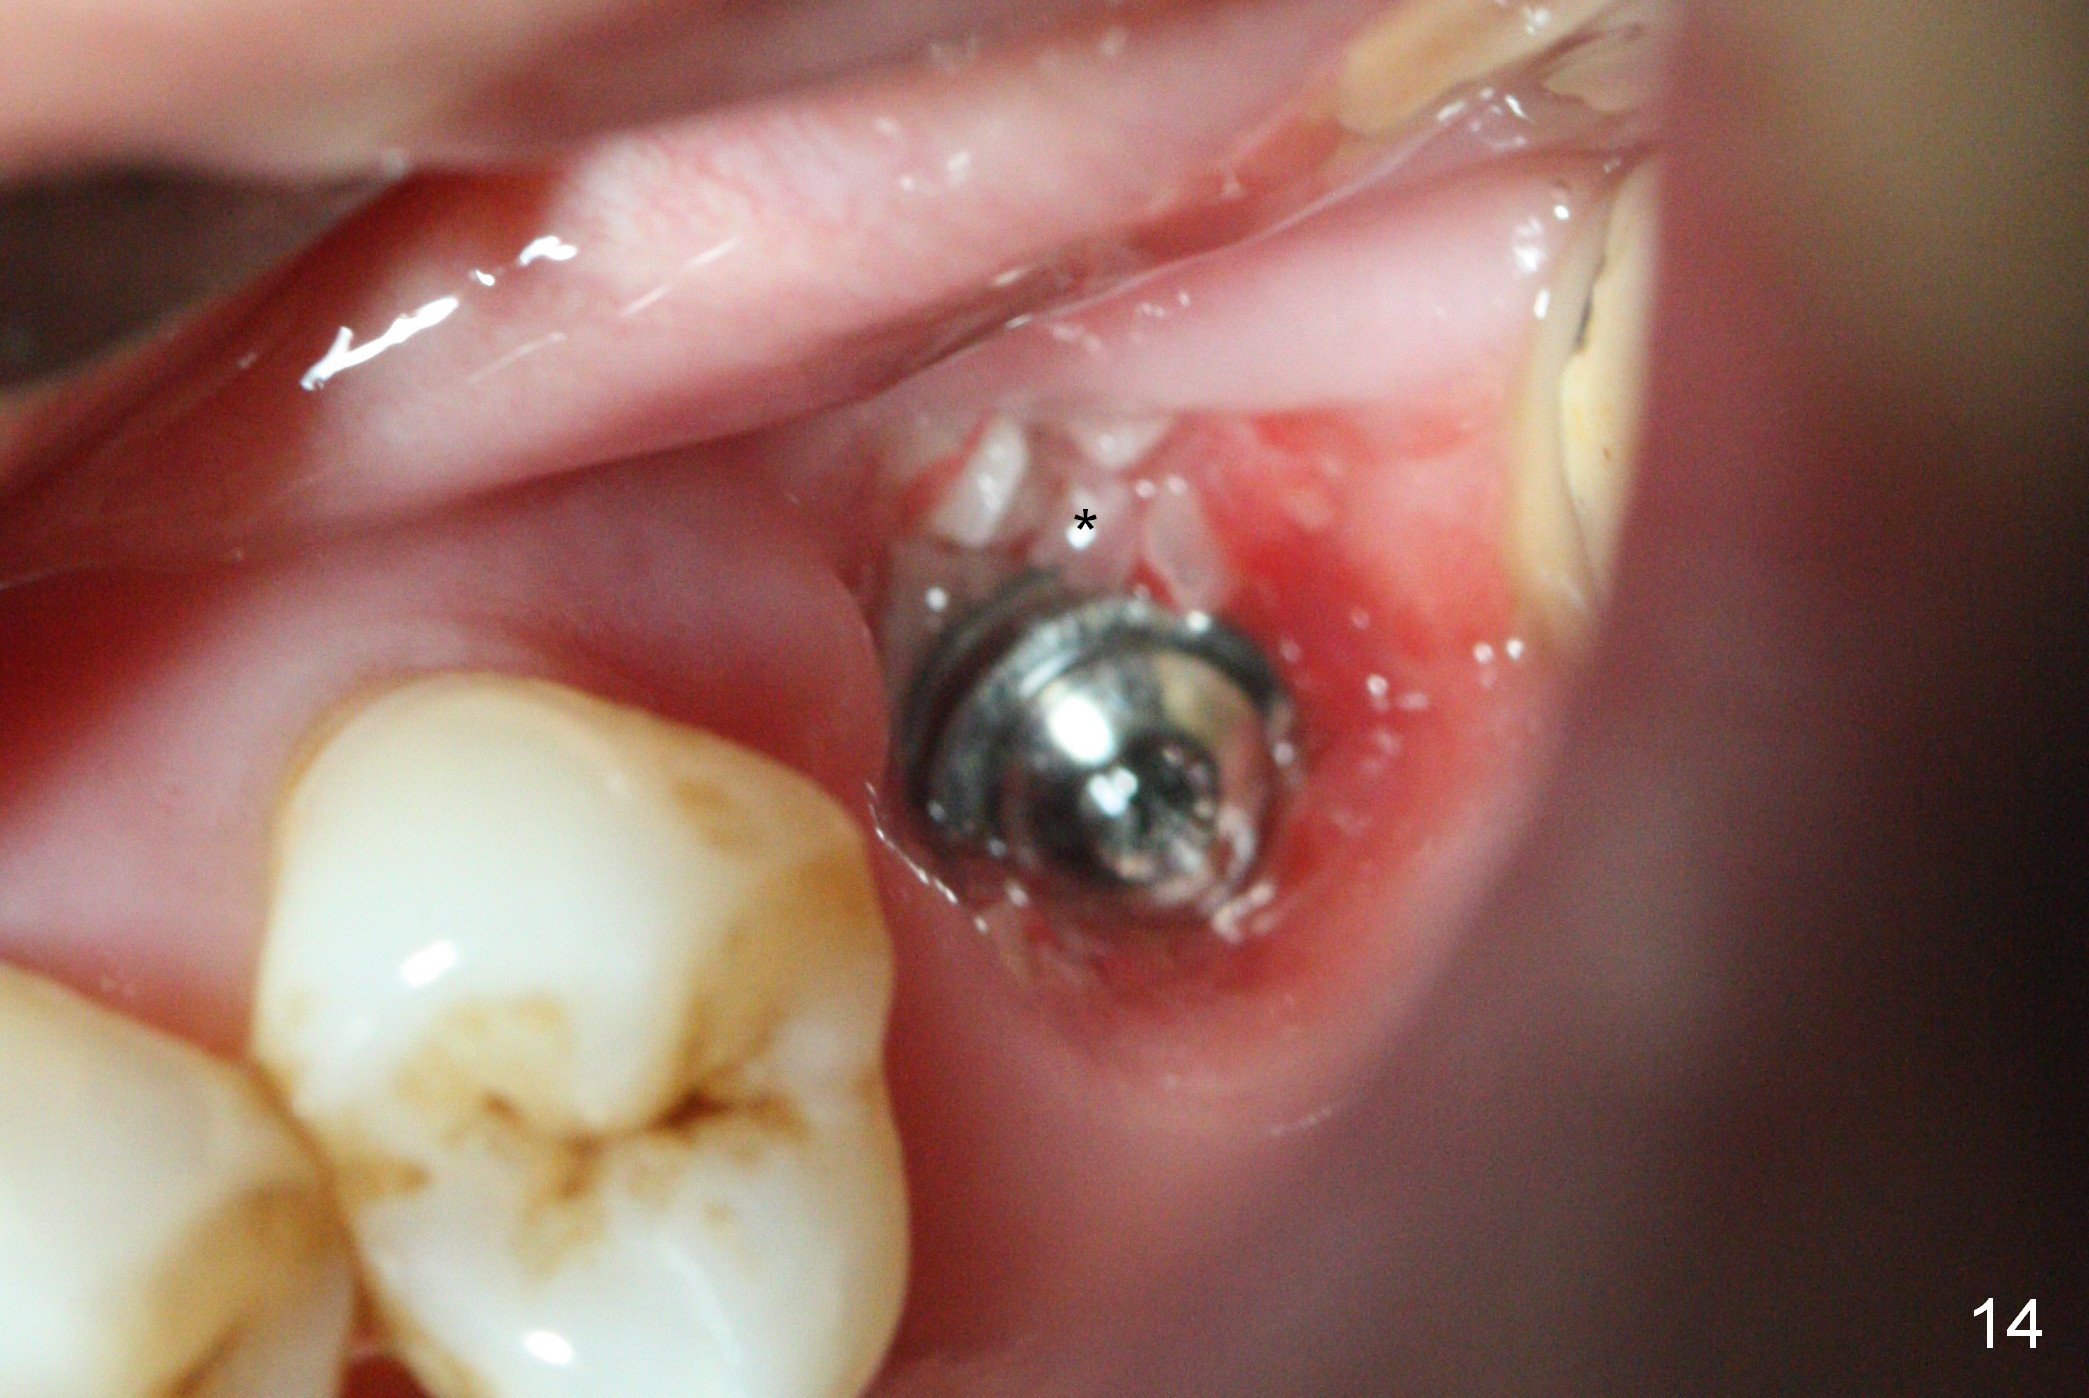

The implant is stable 8 months postop (Fig.15). When a 6x4(3) mm abutment is placed 8.5 months postop, it is distal (Fig.16). The mesiodistal width is 1-2 mm shorter than that at #3, which suggests the mesial shift of the tooth #15. A provisional is fabricated at #14 (Fig.17 P) with supra-occlusion so that there is clearance between the tooth #15 and the opposing one (Fig.18 *). With a separator placed between #14 and 15 (Fig.19), the latter is free to be distalized. Bone volume and density seem to increase 4.5 and 10.5 months post cementation (Fig.20,21, as compared to Fig.15), although the buccal plate remains as concave as shown in Fig.18. One year 5 months post cementation, the patient complains of bad smell from the implant when water pik is being used. It appears that the 1st 2-3 threads are exposed (Fig.22), although the surrounding gingiva remains uninfected. Bone graft is recommended. The site heals without bad smell 7 months post bone graft (2 years 4 months post cementation, Fig.23). The 1st implant thread is found exposed buccal on uncover (regraft?). A small healing abutment is placed because the implant is placed distal (Fig.24). An angled abutment should be tried and #15 crown will be redone. Impression will be taken when the gingiva heals around the provisional crowns.